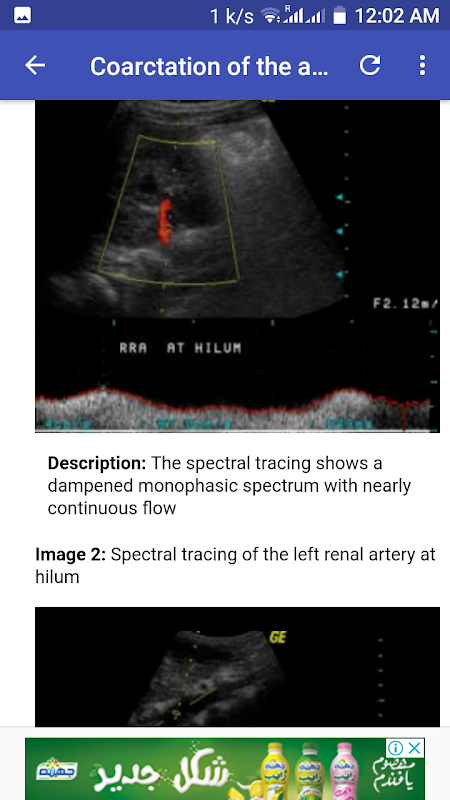

Torsione ovarica destra